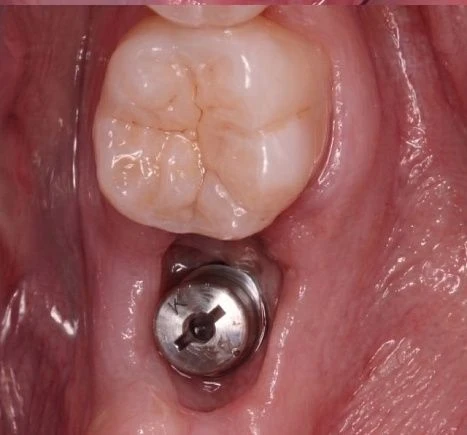

Такие микропротезы можно ставить на жевательные зубы. Часто их используют для установки на импланты.

В клинике «Доктор Смайл» коронки Е-мах используются в следующих случаях:

- имплантация;

- С помощью коронок Е-мах можно как скрыть потемнения и сколы на эмали, так и полностью восстановить сильно разрушенный или отсутствующий зуб.